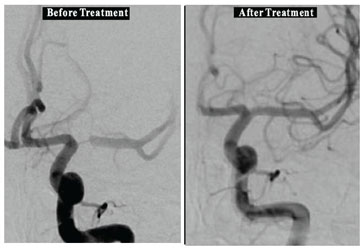

Example- BLOCKAGE A gentleman presented with transient Rt. side facial Paralysis due to more than 95 % blockage of Brain Artery. After removal of blockage by STENTING , he never had these episodes.